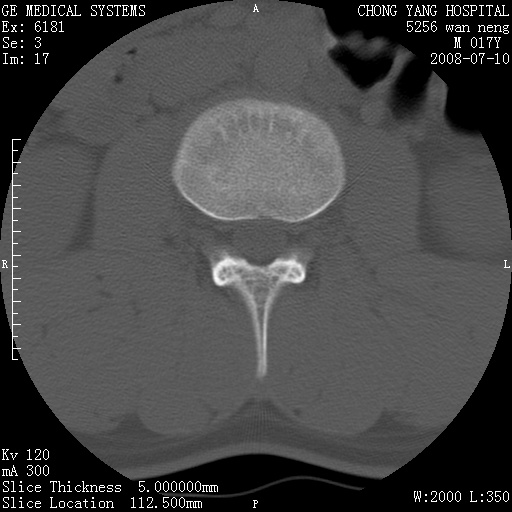

腰3、4椎弓崩裂

腰3、4椎弓不连

支持:腰3、4椎弓峡部崩裂。

腰3、4椎弓峡部不连

支持:腰3、4椎弓峡部崩解。

腰3、4,如受过外伤则为陈旧骨折,否则为骨质不连

图片漂亮,目前也只能看到腰3、4骨质不连

腰3、4椎弓峡部裂。

腰3、4椎弓峡部裂。支持

重建图像见多个椎弓峡部不连(不足为据),平扫未见异常。

支持腰3、4椎弓峡部崩裂。